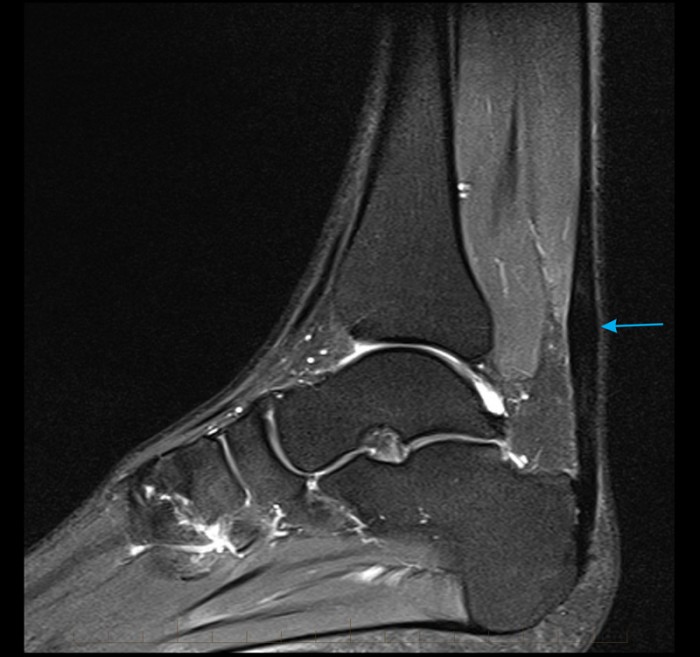

An ankle MRI demonstrates a sagittal STIR image of the Achilles tendon …